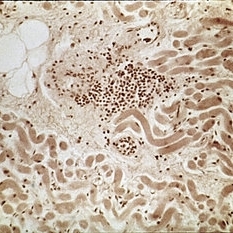

Inflammatory pseudotumor showing polymorphism and ancillary evidence of inflammation. Note presence of lymphocytes, plasma cells, and "juicy" capillaries (H&E x252).

Condition/keywords: lymphocytes, polymorphism, pseudotumor